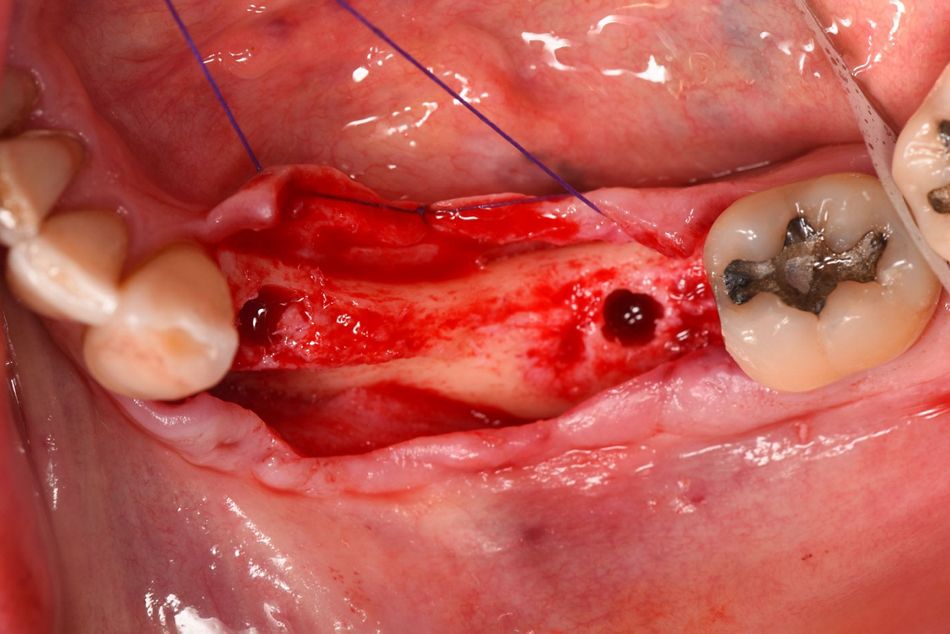

Following local anesthesia (Articain 4% with Adrenalin 1:100.000), mucoperiosteal flaps were raised by means of midcrestal and intrasulcular incisions. The lingual flap was fixed with a suture in order to facilitate the visibility of the area (Figs. 6 & 7).

Moreover, a simultaneous bone augmentation was performed in the vestibular area of implant #34 using the Straumann® Jason Membrane and bone graft. The rational of this horizontal bone augmentation was the thin (less than 1.5 mm) remnant bone on the vestibular area (Fig. 15). The collagen membrane was stabilized with a zirconia healing abutment (RC Ø 4.5mm, H 4mm), whereas for implant #36, a titanium healing abutment (RC Ø 4.5mm, H 4mm), was screwed. The flaps were closed by primary intention by the placement of simple stiches with Vycril 5/0 (Figs.16-20).